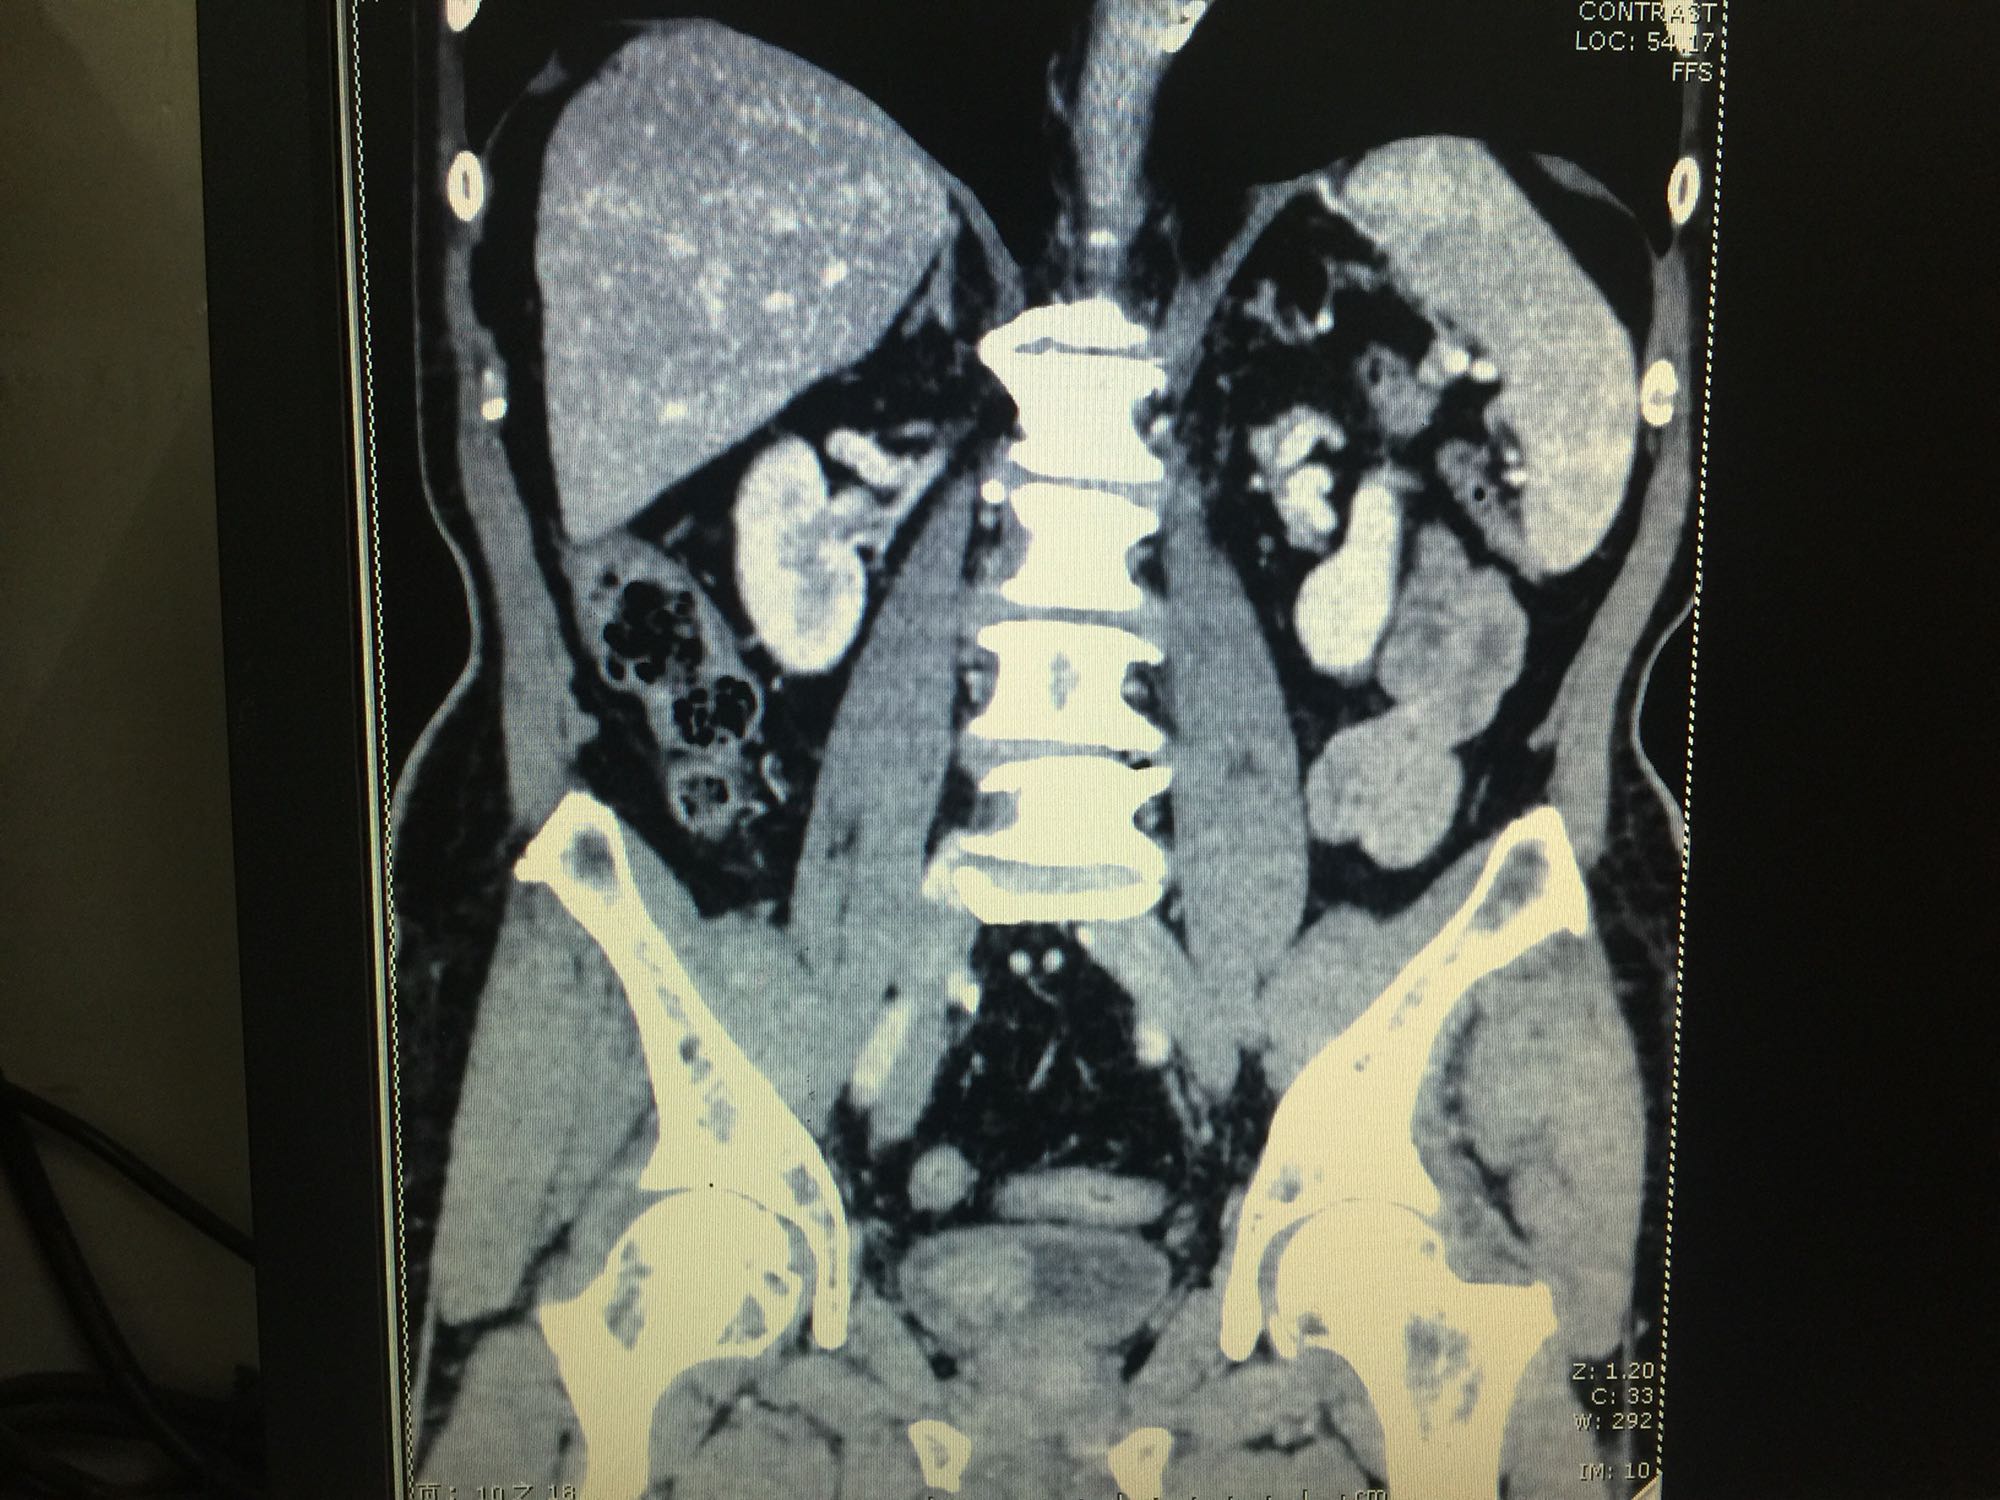

膀胱占位一例

膀胱癌

80岁男性 既往冠心病 血尿3月,发现膀胱新生物2天入院

查体:膀胱无充盈,阴囊无异常,睾丸附睾无肿大。前列腺二度大,质地中等,无压痛等